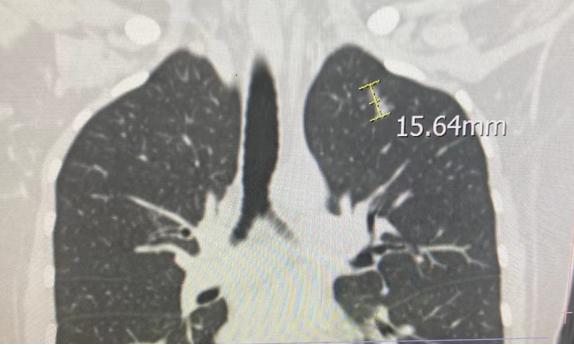

我们今天还找另一个医院的影像科主任帮忙看了一下片子,他说结节看上去像是2个小的融合成的,重建后的图像显示结节长径到了1.5 cm,高度怀疑早期肺癌(最后一张图是重建后的图)。

左肺上叶玻璃结节,接近于纯磨玻璃,形态不规则,长经约35px (重建后测量图像),较2月10日片无变化。高度怀疑早期肺Ca,建议胸外科会诊。